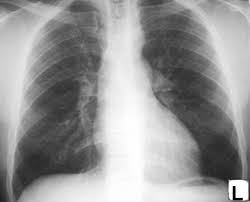

CXR: 우심방, 우심실 확장. 폐혈관 음영 증가 소견

CXR: 심비대, 폐부종